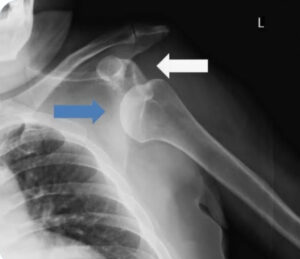

先日、学術大会が千葉県柔道整復師会館(千葉市中央区)にて開催。リモートで参加。各会員の発表、「ラジオ体操のアップデート」「三果骨折の一症例」「ゼロポジション法を用いた肩関節前方脱臼の整復及び後療法」は興味深く視聴させて頂きました。午後は匠の技、これまた、肩関節脱臼の整復法の実技。ヒポクラテス法(踵骨法)の解説。当院も使用する方法ですが、今第一選択ではないとか。スティムソン法(重りぶら下げ法)、コッヘル法等々あります。開業して2.3症例、とんと来院されませんが、元来、未だ、ほねつぎ。心の準備は満タンです